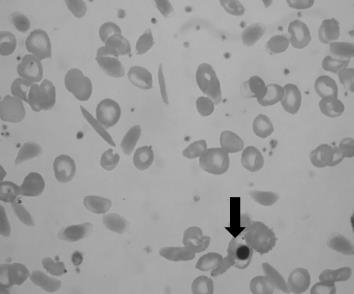

Observe a imagem:

No diagnóstico da anemia falciforme, alguns achados são observáveis no esfregaço de sangue periférico. O indicado pela seta denomina-se: